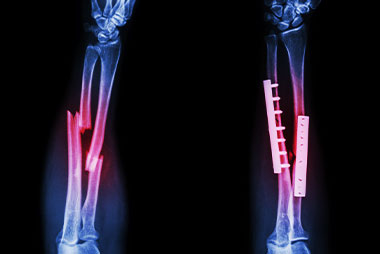

Trauma y Manejo de Fracturas

TALLER DE ESPECIALIZACIÓN Y PERFECCIONAMIENTO

Institución Badra te invita al taller de Trauma y Manejo de Fracturas, dictado por médicos especialistas en Emergentología. El presenta taller pretende abordar, desde el punto de vista de los primeros auxilios, las eventualidades que pueden comprometer la vida del paciente por diferentes fracturas. Los participantes aprenderán a obtener ayuda médica ante una fractura, a hacer uso de férula, las maniobras correspondientes, etc. Te esperamos!

- Introducción y generalidades sobre fracturas.

- Clasificación de las fracturas.

- Complicación de las fracturas.

- Manejo prehospitalario de las fracturas.